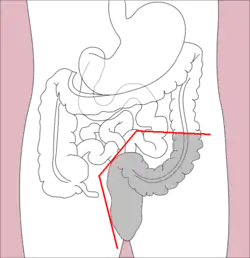

Right hemicolectomy and left hemicolectomy refer to the resection of the ascending colon (right) and the descending colon (left), respectively. When middle colic vessels and transverse colon are also resected, it may be referred to as an extended hemicolectomy.[20] Left hemicolectomy is most commonly indicated for cancer in the splenic flexure or descending colon, diverticular disease of the descending colon, and colovesicular or colovaginal fistulas that develop as a consequence of diverticular disease.[11] The main limitation to performing a left extended colectomy is the difficulty of achieving a colorectal anastomosis afterward. Different techniques, such as Deloyer's or Rosi-Cahil's techniques, have been proposed to solve this issue.[21] Right hemicolectomy is most commonly indicated for masses in the right, or ascending, colon but may also be performed for neoplasms of the cecum or appendix. Right-sided diverticulitis, cecal volvulus, inflammatory bowel disease, and adenomatous polyps are benign conditions that may require right hemicolectomy.[11]